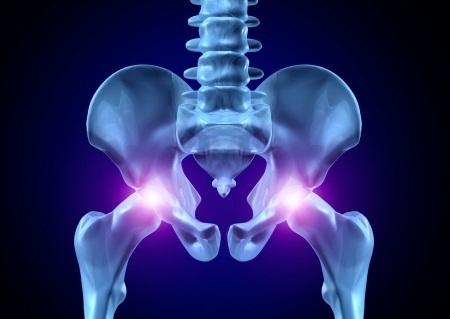

Коксартроз – болезнь, которая вызывается деформацию в тазобедренном суставе. Возникает из-за сильных травм и перенапряжений. Пациенты в любом возрасте подвержены такому заболеванию. Мужчины чаще болеют коксартрозом чем женщины. Необходимо знать причины заболевания, методы лечения и основные симптомы.

Врачи отмечают, что коксартроз, или остеоартрит тазобедренного сустава, проявляется рядом характерных симптомов. К основным из них относятся боли в области бедра, ограничение подвижности сустава и хруст при движении. На ранних стадиях пациенты могут испытывать дискомфорт только при физической нагрузке, однако по мере прогрессирования заболевания боль становится постоянной и может иррадиировать в колено.

Проявление начальной стадии коксартроза обычно не сильно заметно. Пациент ощущает небольшой дискомфорт в зоне суставов. В первые недели нет ни отека, ни опухлости. Врачи выделили такие симптомы болезни: